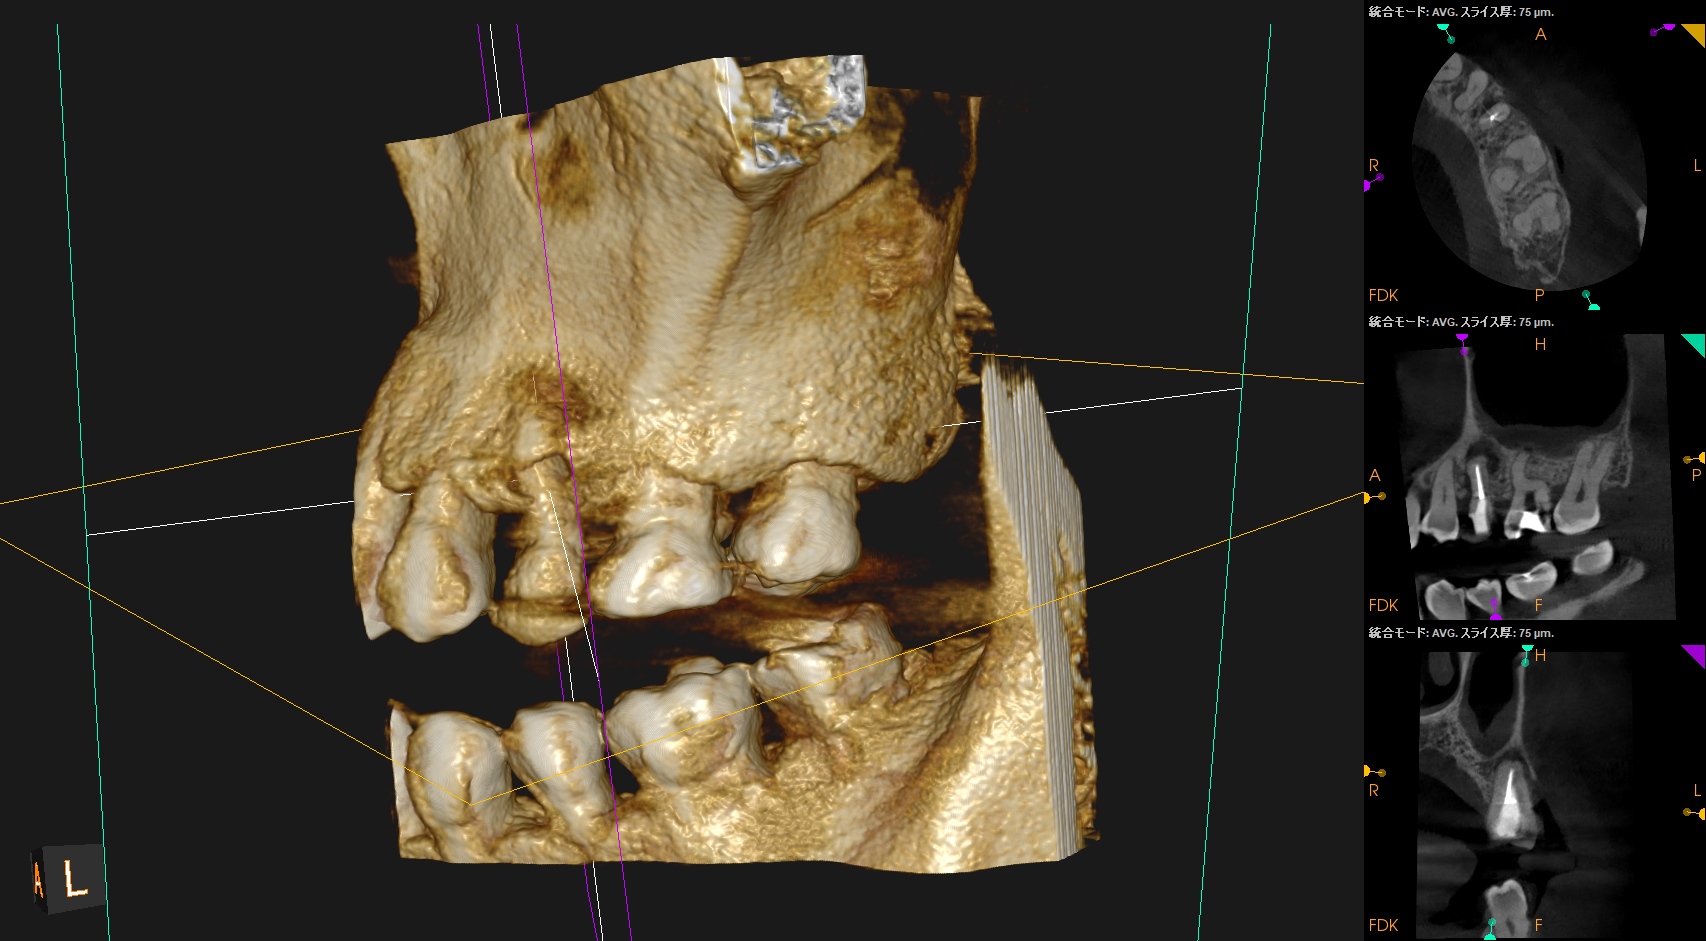

ということで、主訴の#14から再根管治療を行い、残された時間で#13を行うことになった。

その際は、

MB1

MB2

DB

P

#13

おおよその作業長が類推できる。

#14 Re-RCT(2026.4.2)

#13 Re-RCT(2026.4.2)

ということで、術後にPA, CBCTを撮影した。

#14